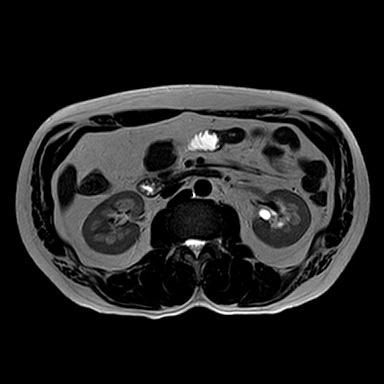

• 비뇨기과를 가시는 것이 맞고, 제공해주신 MRI와 초음파 소견을 종합하면, 양측 신장에 병변이 보이기는 하나 형태가 서로 다릅니다. 한쪽은 비교적 경계가 명확하고 밝게 보이는 병변으로 낭종 가능성이 우선 고려되고, 반대쪽은 내부 신호가 혼재된 형태로 단순 낭종 외의 병변 가능성도 완전히 배제하기는 어렵습니다. 다만 단일 컷 이미지로는 조영 증강 여부, 내부 구조, 혈류 평가가 제한되어 확정 판단은 불가능합니다.

임상적으로 중요한 기준은 단순 낭종인지, 복합 낭종인지, 혹은 고형 종양인지 구분하는 것입니다. 단순 낭종이면 추가 치료 없이 경과관찰이 원칙이고, 복합 낭종이나 고형 병변이면 추가 평가가 필요합니다. 이 구분은 조영증강 CT 또는 조영 MRI에서 보스니악 분류 기준으로 판단합니다.

현 시점에서 급하게 의심할 소견으로 단정하기는 어렵지만, 양측성 병변이므로 단순 낭종인지 확인은 반드시 필요합니다. 특히 40대에서는 우연히 발견되는 낭종이 흔하지만, 복합 낭종은 일부에서 종양과 연관될 수 있어 정밀평가가 필요합니다.